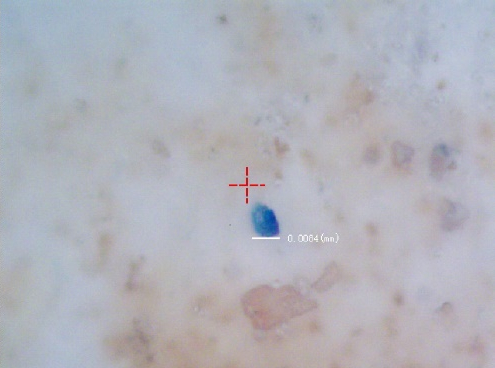

如图1~3所示为赫尔大学研究团队在人体中探测到的塑料的种类(图1)、形状以及显微成像。

图3:微塑料显微成像

结果显示从人体中提取出的微塑料中PP、PET以及树脂占主要成分,且绝大多数微塑料是以碎片以及纤维形式存在于人体中的。

微塑料大小从几微米到100微米不等,由于体积小,随着空气等原因进入身体之后,就会吸附在肺部上。